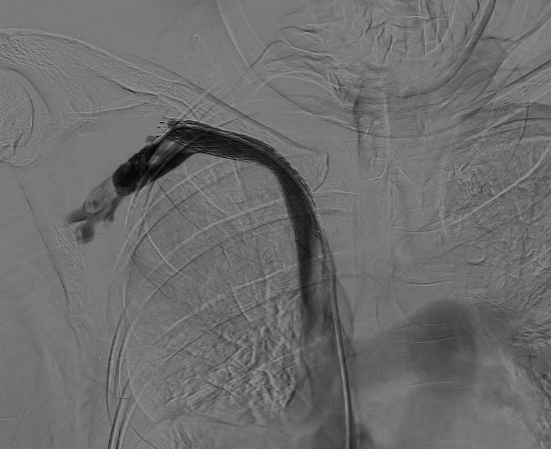

術(shù)前

患者既往有中心靜脈導(dǎo)管置入史,住院期間患者發(fā)現(xiàn)右上肢腫脹,范圍累及整個右上肢,腫脹程度逐漸加重,皮膚張力增高。右上肢靜脈超聲提示:右側(cè)鎖骨下靜脈血栓形成。遂后經(jīng)我院介入科會診并行右上肢靜脈及中心靜脈造影示:右側(cè)鎖骨下靜脈近心端及頭臂靜脈明顯閉塞,右側(cè)鎖骨下靜脈遠心端繼發(fā)血栓形成。

完善各項術(shù)前評估和準備后,介入科韋運豪主治醫(yī)師、熊偉主治醫(yī)師、朱海副主任醫(yī)師及李衡住院醫(yī)師等對患者進行上述手術(shù)方案的操作。術(shù)中將導(dǎo)管成功通過閉塞段血管,再次造影明確閉塞段長度、寬度及鎖骨下靜脈遠心端血栓情況。